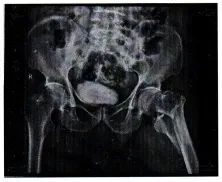

随后,杨某拨打120将李老伯送往医院。经诊断,李老伯左侧股骨转子间骨折,需手术治疗。期间共住院11天,产生医疗费、护理费等8万余元。后经重庆法医验伤所鉴定,李老伯此次受伤属九级伤残。

图为司法鉴定意见书